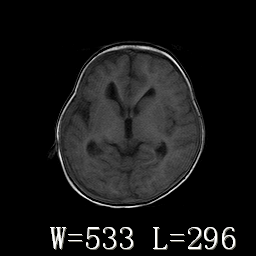

标题: PED3252:脑室增大。

女,3岁,3岁不会说话,阵发性抽搐、自伤。

考虑为梗阻性脑积水(中脑导水管狭窄)。

侧脑室不规则,前后角尖角样,脑白质较少:考虑灰质发育不良可能

倒数第3附图不是这个病人的吧!考虑脑白质发育不良可能。

右侧额叶发育不良!

右侧额叶发育不良。

右侧额叶发育不良

考虑,脑发育不良,胼胝体发育不全?(图片不全,矢状位?)